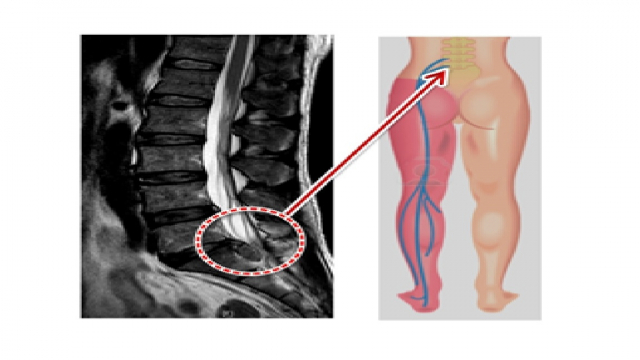

서울대 재활의학과 교수님이 쓴 책의 내용인데 1주일에 20km 이상을 달리는 사람과 운동은 하지 않는 사람들을 비교해 봤을 때, MRI 영상에서 달리기를 꾸준히 하는 사람들이 허리디스크가 두꺼웠고 그 속의 수분 함유하고 있는 분량이 높았다는 내용이 있었습니다.